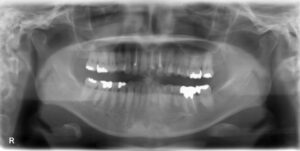

• 下顎大臼歯1本欠損症例

BEFORE AFTER 53歳女性/下1本欠損/インプラント埋込手術 【治療内容】 歯根の先で炎症が広がり、抜歯となっ…